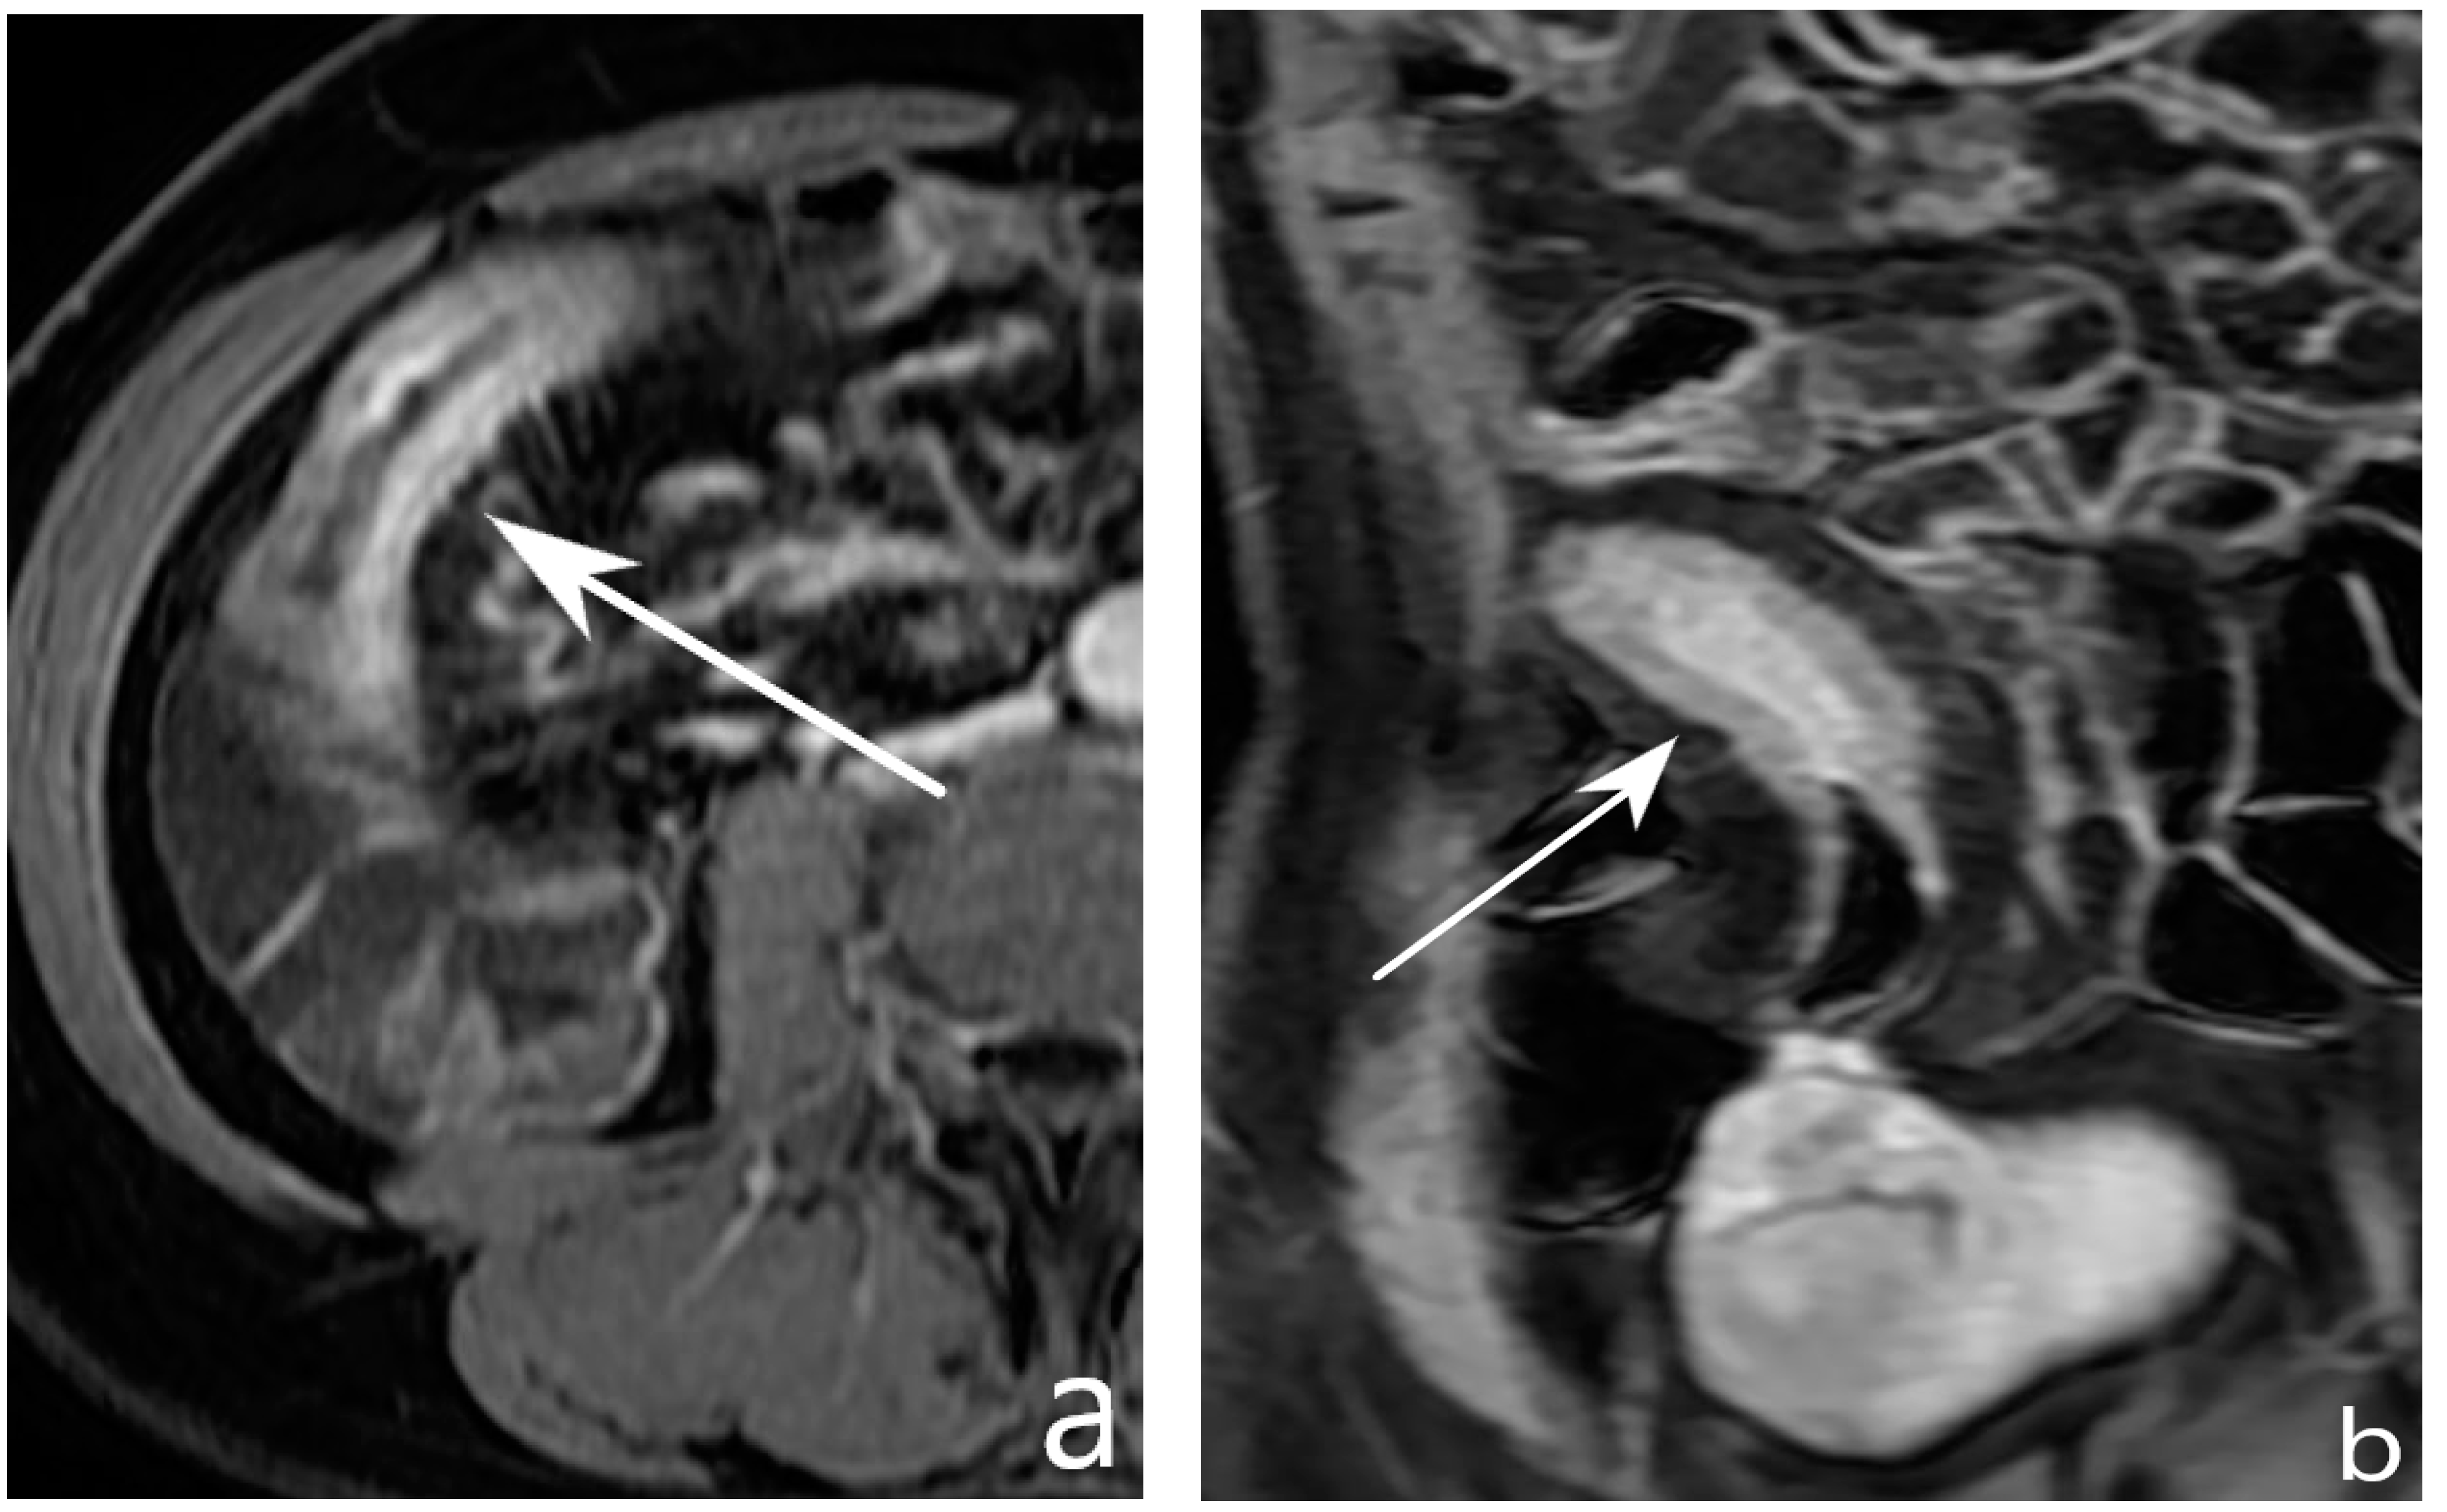

9. Is It Possible to Assess Post-Operative Recurrence?